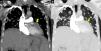

A 65-year-old man with a histopathologic diagnosis of hepatic alveolar echinococcus ten years ago presented with progressive dyspnea. The patient's electrocardiogram showed atrial fibrillation. Radiologic evaluation revealed extensive metastases in bilateral lungs and cardiac involvement secondary to echinococcus alveolaris (Fig. 1). The patient was followed for pulmonary metastases for about 10 years. Slow progression of pulmonary metastases was observed over time. However, cardiac involvement recently appeared. The patient was given albendazole 10mg/kg/day for three months every year and was followed up.